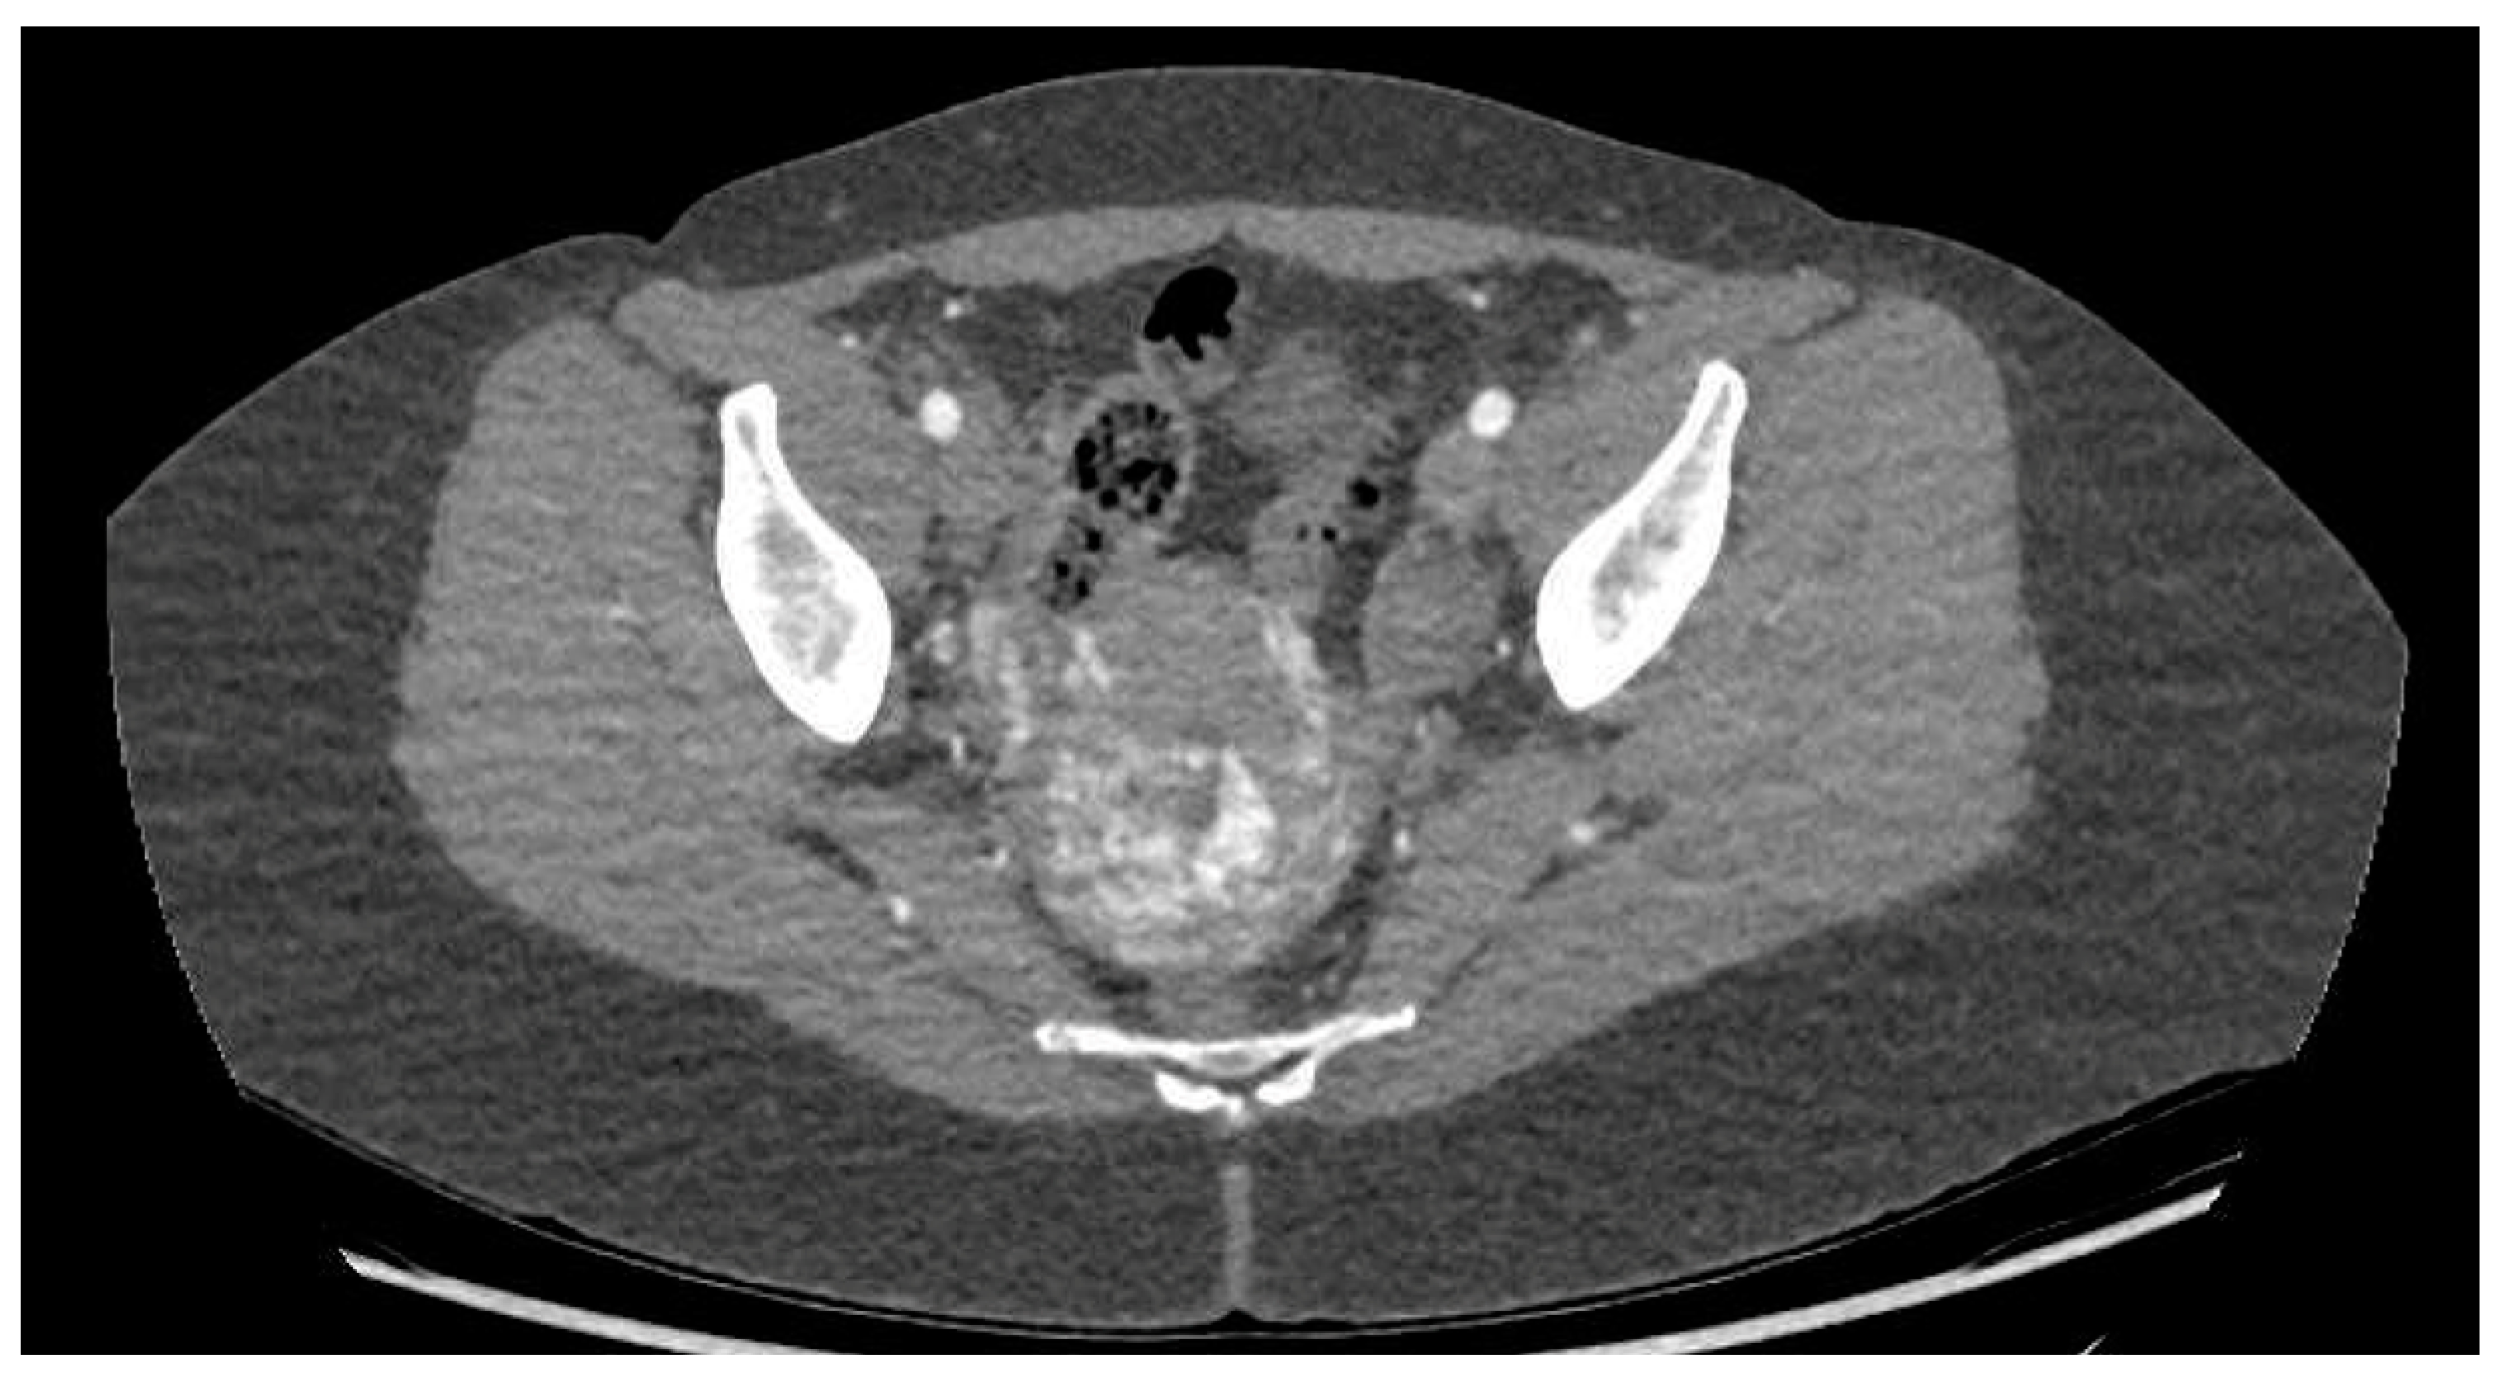

CT angiography showed a complex network of millimetre-sized vessels of tortuous appearance with rapid contrast enhancement in the late arterial phase and isodensity in the portal phase (similar to systemic venous vessels). This network extended through the right parametrium, through the myometrial fundus, and apparently into the endometrium (Figure 3 and Figure 4). The radiological findings were compatible with a uterine arteriovenous malformation.

Figure 3. Cross-sectional pelvic CT angiography.